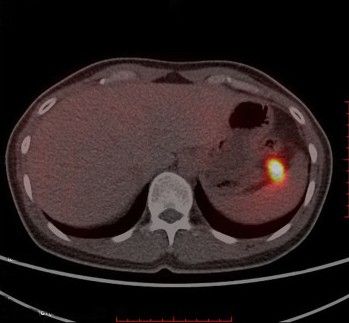

- Из-за малых размеров инсулинома не всегда видна на изображениях, поэтому разрабатываются новые методы диагностики этого заболевания. Среди них можно выделить радионуклидные, при которых в организм вводят радиоактивные вещества и после этого измеряют излучение, исходящее из органов и тканей. Для этого проводят позитронно-эмиссионную томографию (ПЭТ) и КТ с препаратом 68Ga-DOTA-exendin-4. Сейчас этот метод применяется только в рамках клинических исследований, но из-за высокой чувствительности и специфичности может быть внедрён в клиническую практику [8].

Выявление инсулиномы в поджелудочной железе при 68Ga-DOTA-exendin-4 ПЭТ/КТ [18]